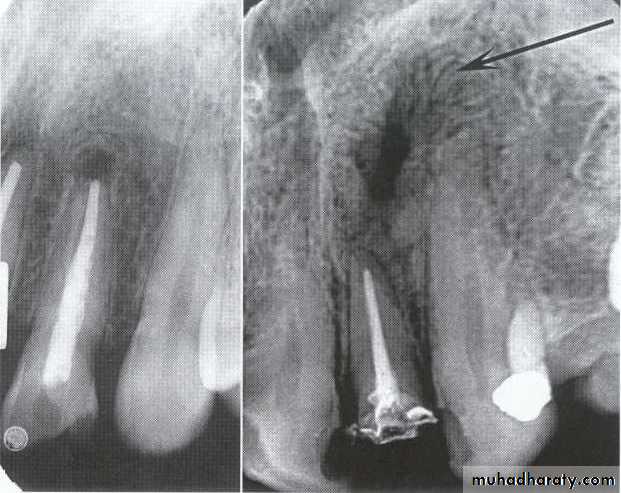

Radiolucency at apex of endodontically treated tooth

A: Radiolucent apical scar left after successful endodontic treatment..

B:New bone forming from the periphery of theLesion.

If the R.L.enlarged, pain,sinus,or no regression in the size of lesion after 6months (P. A. Cyst).

A

B

Apical scar